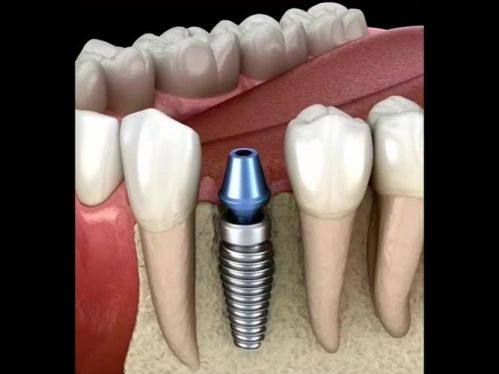

种牙过程主要分为骨结合期和修复阶段,每个阶段的时间也有所不同。

骨结合期:这个阶段是种植体与颌骨融合的时期,通常需要2 - 3个月。在这段时间里,种植体就像一颗种子,要在颌骨里扎根生长。为了让种植体更好地与颌骨结合,患者在这个阶段要避免咬硬物,不然可能会影响种植体的稳定性。如果患者的骨质较差,骨结合的时间可能会延长至4个月。因为骨质不好,种植体与颌骨融合的过程会更慢一些。